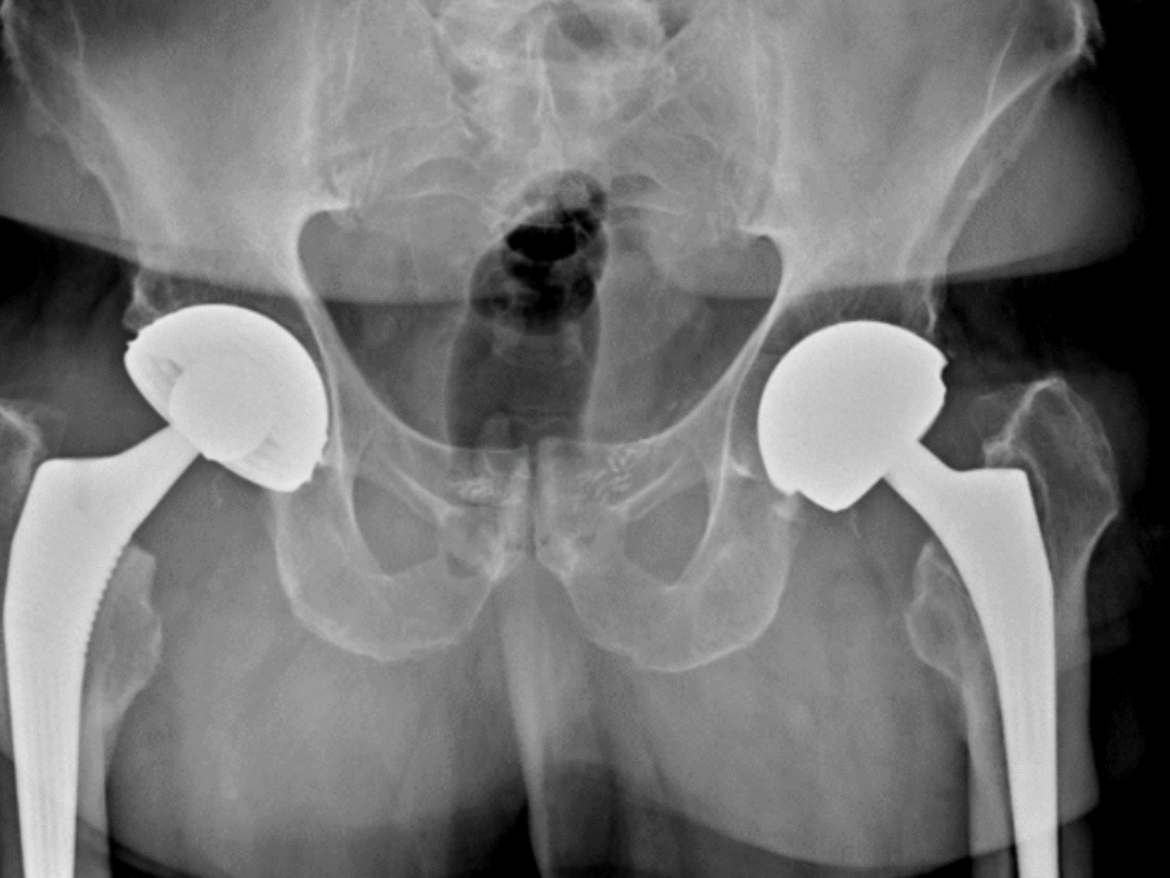

Une attention particulière est portée à la chirurgie mini-invasive, dont l’arthroscopie de la hanche, la prothèse de hanche par voie antérieure, l’arthroscopie du genou, l’arthroscopie de l’épaule et la chirurgie percutanée.

Publié sur Rach LalaouiTrustindex vérifie que la source originale de l'avis est Google. J ai subi une operation de prothese de hanche par voie mini invasive et je conseille vraiment cette technique ou le dr issa exel pas de reeducation kiné juste de marche plus aucune douleurs du super travail du dr issa.Publié sur Alain GuilleminaultTrustindex vérifie que la source originale de l'avis est Google. Excellente expertise, le docteur Issa m'a opéré et posé une prothèse de hanche. Trois mois après je revis, terminé les douleurs lombaires, sciatalgique, cuisse, genou, mollet, pied. D'une très grande gentillesse il a su s'entourer d'une équipe formidable qui débute dès le premier rendez vous avec son secrétariat puis ses collaborateurs et même toute la prise en charge de la clinique Bizet. Sur la table d'opération avant de m'endormir je lui ai demandé pour plaisanter de faire 120% et je crois bien qu'il l'a fait. Bravo.Publié sur Lorenzo PaduanoTrustindex vérifie que la source originale de l'avis est Google. Chirurgien orthopédiste très professionnel, gentil et à l’écoute. Il a réalisé une suture du ménisque de mon genou avec un résultat parfait, malgré une situation assez complexe que d’autres médecins n’avaient pas bien identifiée. Avant l’opération, il m’a expliqué tout le processus de manière claire et rassurante. Plusieurs mois après, mon genou est revenu à la perfection. Je me suis senti suivi avec sérieux et humanité. Je recommande sans hésitation.Publié sur Momo MikiTrustindex vérifie que la source originale de l'avis est Google. Moi mourad el ardi j'ai étais opéré des hanches le 19 janvier part docteur issa je tiens à le remercier énormément , je le conseil vraiment chirurgien de qualité et je le remercie énormément de son professionnalisme très très très content merci beaucoup docteurPublié sur athef najah mejaiTrustindex vérifie que la source originale de l'avis est Google. J’ai été opéré d’une suture de la coiffe des rotateurs par ce chirurgien et je le recommande vivement. C’est un excellent professionnel, très à l’écoute, avec des explications claires avant et après l’opération. Le suivi a été irréprochable tout au long de la convalescence. Aujourd’hui, 7 mois après l’intervention, j’ai récupéré près de 90 % de mes capacités, avec une nette amélioration de la mobilité et beaucoup moins de douleurs. Un grand merci au docteur ISSA pour votre sérieux et votre professionnalisme.Publié sur Makrame KHABIRTrustindex vérifie que la source originale de l'avis est Google. Super chirurgien, très sympathique. Il explique tout simplement , merci encore :)Publié sur Hindaty DiabateTrustindex vérifie que la source originale de l'avis est Google. Bonjour je suis tellement contente avec mes protèzes de genoux que jai fais lintervation precisement le 22 Septembe 2025 il ya juste 3 mois vraiment une très bonne satisfaction je recommende tout le monde de venir decouvrir le docteur Majed issa un très bon. Chirugien Orthopediste Merci meilleur santé as tout ce qui souffre dartrose du dos des épaules les genoux etcPublié sur Mortadha Ben BaballahTrustindex vérifie que la source originale de l'avis est Google. Cela fait un mois que j’ai été opéré d’une désinsertion des adducteurs, plus précisément du long adducteur et du petit adducteur, suite à une blessure survenue au handball. Aujourd’hui, je tiens à exprimer toute ma gratitude. L’intervention, pourtant délicate, s’est déroulée parfaitement : mes adducteurs vont très bien, la récupération est propre et la cicatrice est quasiment invisible, on dirait que je n’ai jamais été opéré. Merci du fond du cœur au Dr Majed ISSA. J’avais vraiment peur avant l’opération, mais son professionnalisme, sa précision et son humanité m’ont complètement rassuré. Grâce à lui, cette expérience est devenue un vrai soulagement. Et un grand merci également à sa secrétaire pour son accueil chaleureux et sa gentillessePublié sur Na KhaTrustindex vérifie que la source originale de l'avis est Google. Un grand merci au Dr Majed Issa pour son écoute, son attention et son professionnalisme. Après cinq ans de consultations sans réponse, c’est le seul médecin qui a su identifier mon problème. Souffrant d’un conflit des hanches, il a pris le temps de réaliser plusieurs examens et d’essayer différentes solutions avant de proposer l’opération. Rien n’a été précipité, tout a été fait avec soin. L’intervention s’est très bien passée, la cicatrice est discrète et je suis pleinement satisfaite. Un grand merci à lui pour sa compétence, son humanité et son dévouement. Je le recommande vivement. Merci également à sa secrétaire Sonia qui est à l image du chirurgien : bienveillante et à l’écoute.Certifié par: TrustindexLe badge vérifié de Trustindex est le symbole universel de confiance. Seules les meilleures entreprises peuvent obtenir le badge vérifié, avec une note supérieure à 4.5, basée sur les avis des clients au cours des derniers 12 mois. En savoir plus